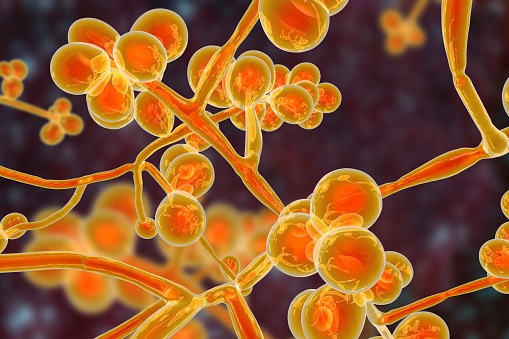

A study published in Nature found that the movement of certain fungi from the gut to the pancreas can increase the risk ...Kerri FitzgeraldEsophageal Cancer | March 19, 2025